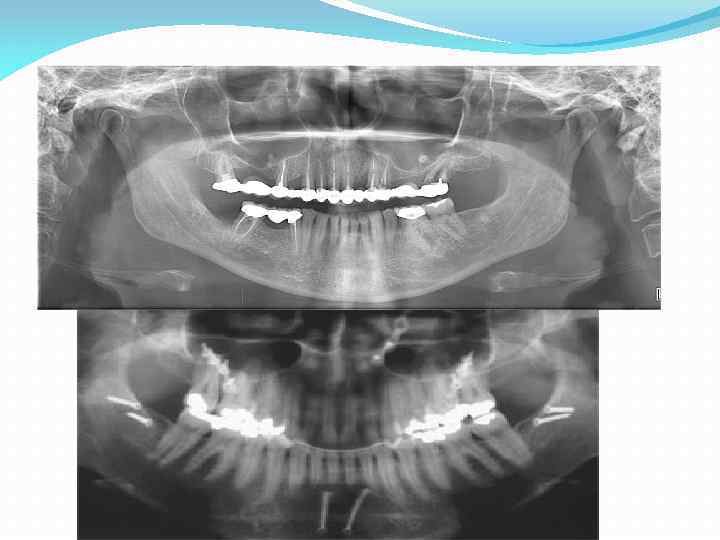

Рентгенологические методы исследования Большое значение в диагностике заболеваний височнонижнечелюстного сустава придается рентгенологическим методам исследования. Обзорная рентгенограмма, ортопантомография дают лишь общее представление о височно-нижнечелюстном суставе ввиду проекционных искажений и наслоения других костей лицевого и мозгового черепа (скуловой дуги, пирамиды височной кости, позвонков и т. д. ). Однако этот метод исследования дает возможность распознавания ряда заболеваний (вывихи, подвывихи, артрозы, переломы суставного отростка и др. ).